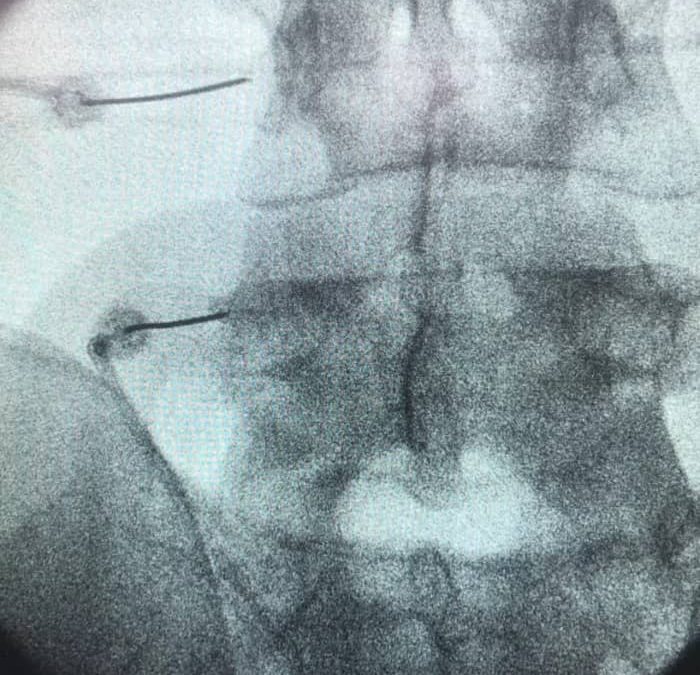

La radiofrecuencia de la articulación sacroilíaca es un tratamiento mínimamente invasivo que puede proporcionar alivio a largo plazo del dolor en casos de sacroilitis. Este procedimiento implica el uso de ondas de radio para generar calor y perturbar las funciones nerviosas que envían señales de dolor a la articulación.

A menudo se realiza bajo la guía de rayos X para una precisión óptima. Aunque los resultados pueden variar de un paciente a otro, muchos experimentan una disminución significativa del dolor y una mejora en su calidad de vida tras el tratamiento.